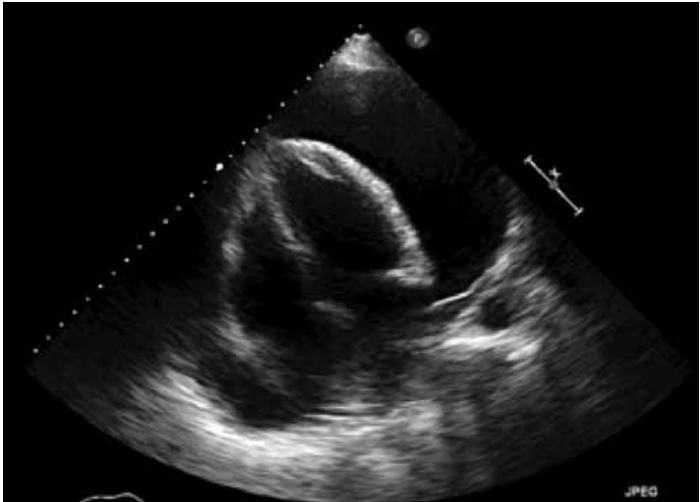

Mulher, 70 anos, com câncer de mama em quimioterapia, queixa-se de dispneia a mínimos esforços nos últimos dois dias. Apresenta frequência cardíaca de 110 bpm e pressão arterial de 90x50 mmHg. Realiza ecocardiograma que mostra a imagem a seguir.

Assinale a alternativa que contém achado do ecocardiograma que indica a necessidade de punção pericárdica urgente.